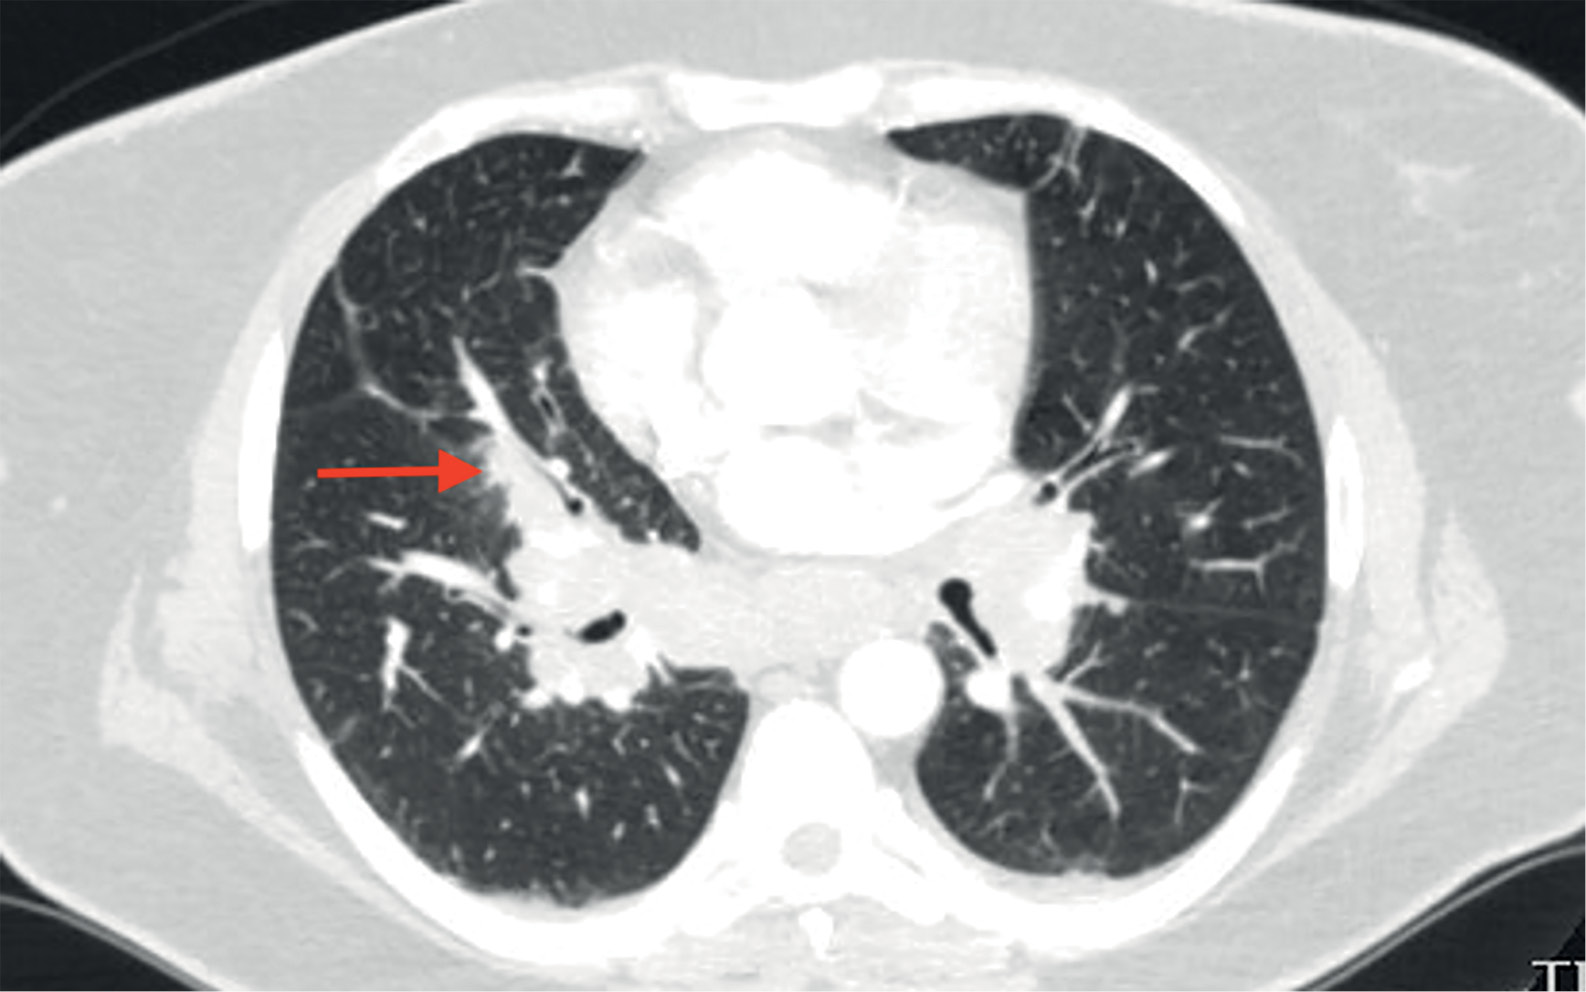

При КТ органов грудной клетки (рис. 2, 3) выявлены множественные мелкоочаговые затемнения в легочной паренхиме лимфогенного распределения, немногочисленные ретикулярные затемнения, уплотнение перибронховаскулярного интерстиция и увеличение лимфоузлов средостения и корней легких, т.е. симптомокомплекс, высокоспецифичный для острой формы саркоидоза. Лабораторные данные подтвердили активность системного воспаления: скорость оседания эритроцитов (СОЭ) 42 мм/ч (0–20), уровень С-реактивного белка (СРБ) был повышен до 7,23 мг/л (норма 0,01–4,99). Уровень кальция крови был в пределах нормальных значений. Проводилась дифференциальная диагностика с туберкулезом органов дыхания и лимфопролиферативными заболеваниями, результаты обследования пациентки и оценка течения заболевания позволили исключить эти заболевания.

Рисунок 2. Саркоидоз легких и внутригрудных лимфоузлов у пациентки М.

Невыраженное уплотнение перибронховаскулярного интерстиция

(указано стрелкой).

Синдром Лефгрена предполагает наличие симптомокомплекса, включающего узловатую эритему, артриты, повышение температуры и рентгенологические изменения в виде внутригрудной лимфаденопатии [20]. На КТ органов грудной клетки при синдроме Лефгрена возможна визуализация поражения легочной паренхимы вследствие ее вовлечения при саркоидозе. Наряду с характерным для синдрома Лефгрена увеличением внутригрудных лимфоузлов, на КТ легких у нашей пациентки выявлялись интерстициальные изменения в легочной паренхиме (мелкоочаговые и ретикулярные тени), не исчезнувшие в течение более 1 года, что свидетельствует в пользу трансформации острой формы саркоидоза в хроническую [20]. Лабораторные тесты при синдроме Лефгрена выявляют признаки повышения острофазовых показателей воспаления в крови (СОЭ, СРБ). Показатели функции внешнего дыхания, легочной диффузии, результаты тестов толерантности к нагрузке при синдроме Лефгрена, как правило, соответствуют нормальным показателям и не являются методом диагностики заболевания, поэтому эти исследования у данной пациентки не проводились.